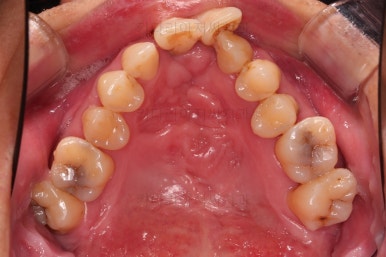

1. 초진 시 입안의 모습

부산구순구개열교정 키다리아저씨치과에 처음 내원하셨을 당시의 입안의 모습입니다.

이번 환자분도 이와 같은 일반적인 특징이 그대로 나타나 있었습니다.

양측성 구순구개열이었으므로 작은 앞니(대문니와 송곳니 사이)가 양쪽 다 결손이었고, 또 다른 이유로 아래 앞니도 1개 없는 상태였습니다.

윗니 2개, 아랫니 1개가 결손이었기 때문에 보철로 추가적으로 치아를 해 넣을지의 여부가 매우 중요했는데요

✅ 추가로 치아를 해 넣지 않고, 현재 치아만으로 교합을 맞추기로 했습니다.

결손 부위의 잇몸뼈의 상태가 썩 좋지 못하며, 대문니 2개의 상태도 장기적으로는 좋지 못할 것으로 예상되어 굳이 주위 치아에 힘을 많이 가하면서까지 공간을 확보하고 치아를 해 넣을 필요는 없다고 판단되었고요.

대신, 치아의 갯수가 위아래가 맞지 않아서 생기는 약간의 애매한 교합 부분은 감수하기로 했습니다.

✅ 악궁확장도 하지 않기로 했습니다.

앞서 입안의 모습에서 위턱뼈의 가로폭이 좁다라는 말씀을 드렸는데요.

잇몸의 베이스가 되는 골격 자체가 좁은 경우

어금니쪽은 괜찮은데, 앞쪽으로 올수록 골격이 좁아지는 경우

베이스가 되는 골격은 괜찮으나 치열이 안쪽으로 쏠려 있어서 좁게 평가된 경우

세 경우 각각 사용하는 장치가 모두 다르며, 이번 환자분은 3번에 가까웠습니다.

치아를 해넣을지 말지에 따라서도 1, 2, 3이 구분되게 되는데요.

어쨌든 이번 환자분은 적극적인 악궁확장 장치까지는 필요 없었고, 브라켓-와이어로만 부산구순구개열교정으로 개선해 보기로 했습니다.